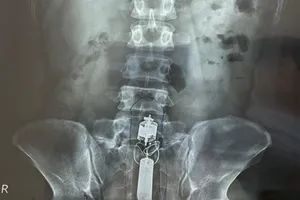

Giải cứu nam thanh niên bị kẹt dương vật giả trong trực tràng

Cứu thanh niên bị mắc kẹt 'của quý' giả